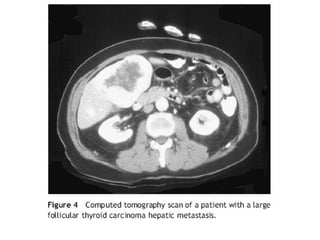

 6% al 23% del total de pacientes con CA

diferenciado, desarrollan metástasis a distancia.

 1% al 4% son evidentes al momento del diagnóstico.

 Pacientes con mets a distancia tienen una sobrevida

a 5 años del 50%.

 El sitio más frecuente es el pulmón, seguidos de

hueso, menos frecuentes, cerebro, hígado y piel.

• 61.

 6% al23% del total de pacientes con CA diferenciado, desarrollan metástasis a distancia.  1% al 4% son evidentes al momento del diagnóstico.  Pacientes con mets a distancia tienen una sobrevida a 5 años del 50%.  El sitio más frecuente es el pulmón, seguidos de hueso, menos frecuentes, cerebro, hígado y piel.  Factores que predicen un peor pronóstico son:  Síntomas, edad >45 años, y poco captación de yodo.